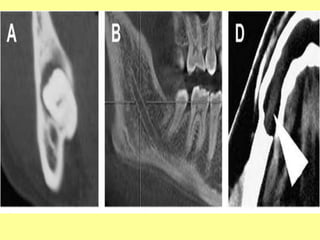

A

B

C

A)coronal, B) sagittal, C) axial.

Images: adapted from (CBCT atlas (1918)).

Three-dimensional reformatted CBCT showing the course of the

inferior alveolar canal between the impacted third molar roots.

C A)coronal, B) sagittal,C) axial. Images: adapted from (CBCT atlas (1918)).

Three-dimensional reformatted CBCTshowing the course of the inferior alveolar canal between the impacted third molar roots.